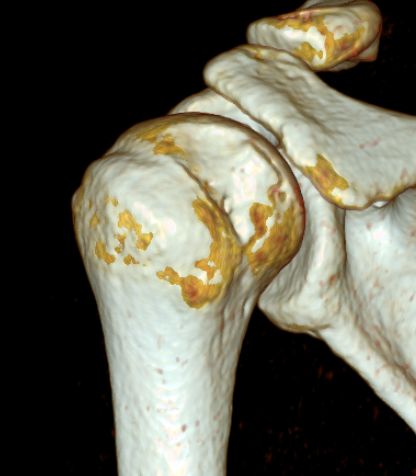

Bone block positioning

Concepts

- coracoid must not overhang medial to avoid osteoarthritis

- coracoid < 5 mm medial to glenoid rim

- coracoid lower half of glenoid 2 - 5 o'clock

Osteoarthritis

Nonunion with failure of fixation / recurrent instability

Nonunion with failure of fixation

Latarjet nonunion with hardware failure and displacement of coracoid fragment